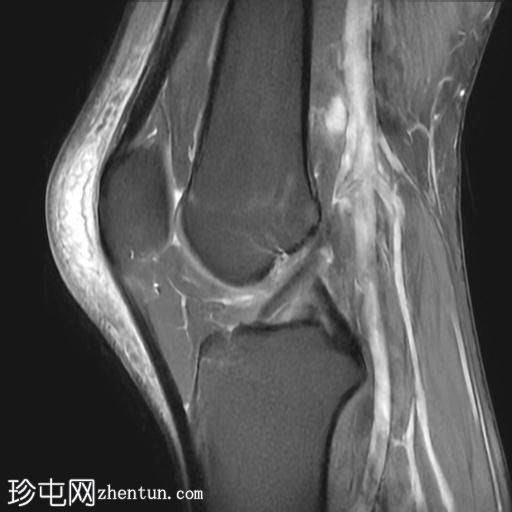

MRI

矢状位

T1加权像

T2加权像

PD脂肪抑制像

冠状位PD脂肪抑制像

轴位PD脂肪抑制像

髌骨前方可见一个卵圆形、充满液体的厚壁囊状物,伴有邻近皮下脂肪间隙水肿和脂肪条索影。

关节积液量极少。

内侧半月板体部及后角可见II级水平撕裂。

此外,外侧半月板体部可见局灶性放射状撕裂。

髌前滑囊炎是指髌前滑囊(位于髌骨与覆盖的皮下组织之间)的炎症和积液。